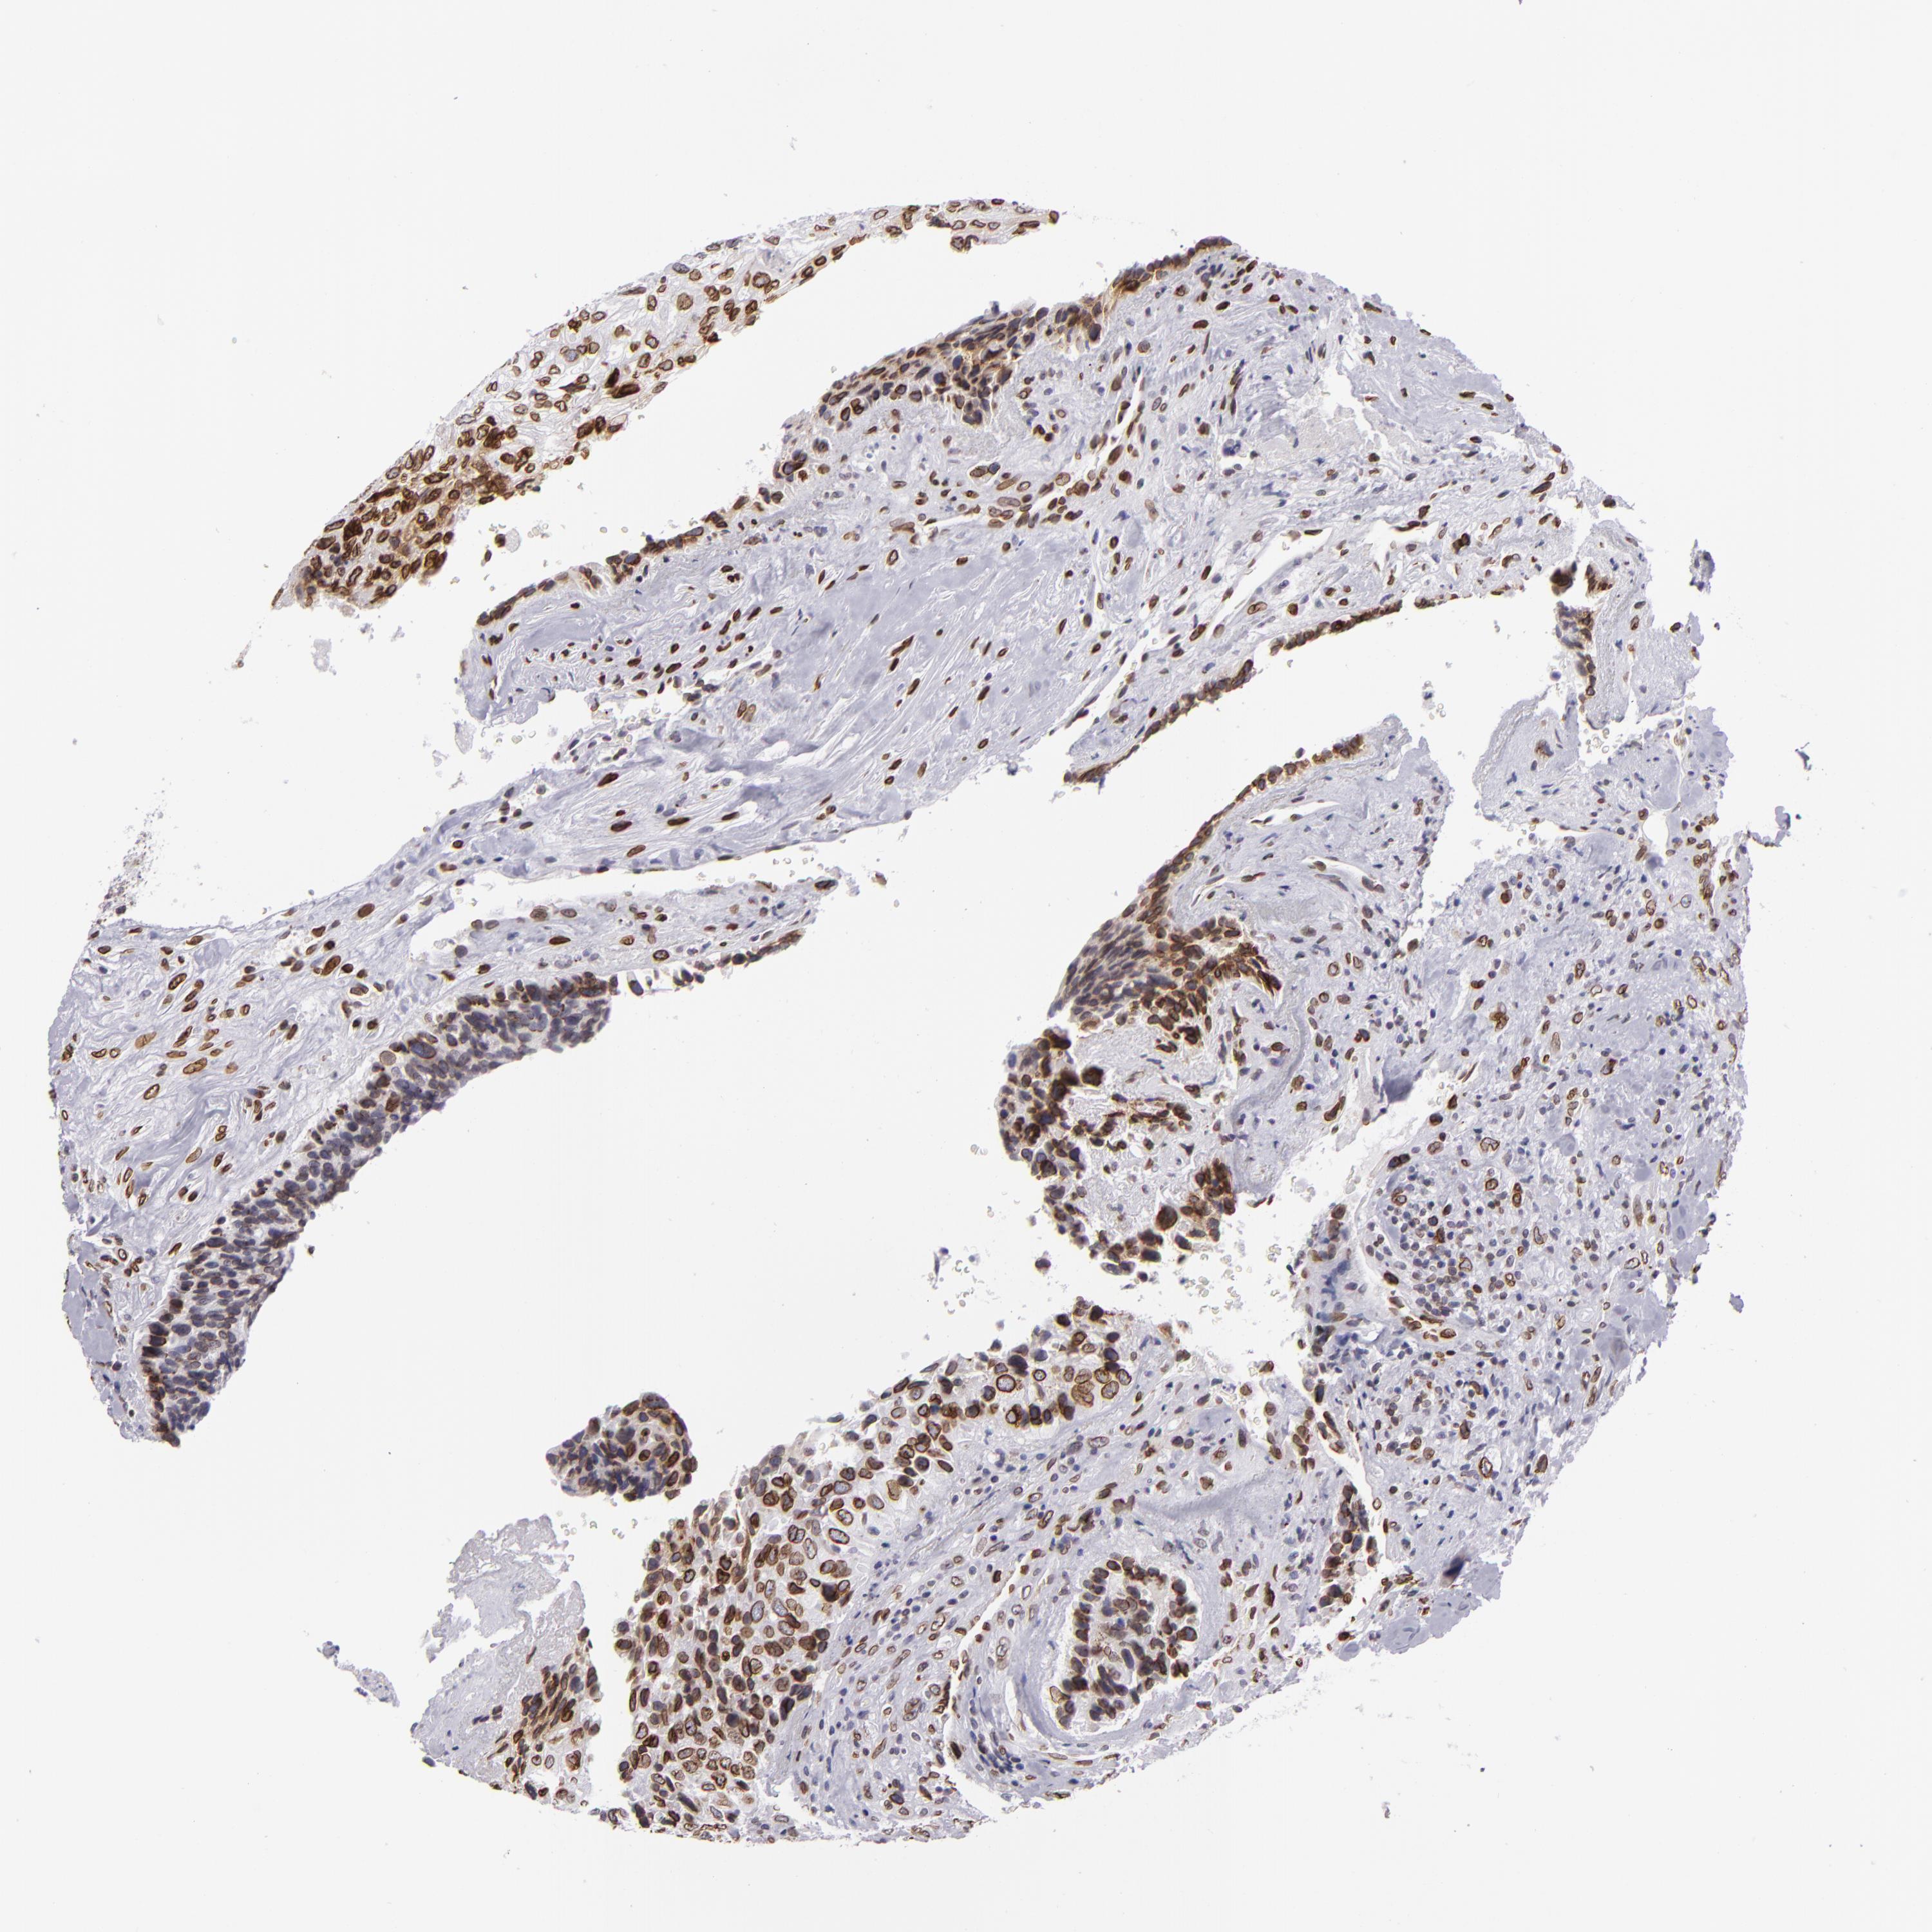

CANCER BREAST CANCER Show tissue menu

BRCA TCGA BRCA VALIDATION PROTEIN EXPRESSION